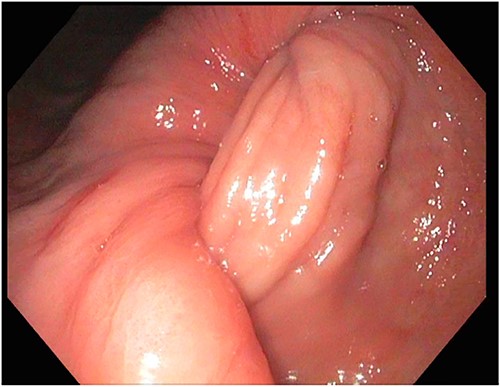

A 72-year-old patient with no past surgical history and a past medical history of developmental delay, hypertension and hyperlipidemia presented to the Emergency Department in mild distress with periumbilical abdominal pain, nausea and intractable vomiting for 1 day. The patient denied any hematemesis, bowel changes, fever, melena or hematochezia. On physical exam, the abdomen was unremarkable, and a computed tomography (CT) scan with contrast of abdomen and pelvis revealed a 5.6 × 5.3 cm heterogeneous mass arising from the body of the stomach extending into pylorus with no evidence of bowel obstruction and liver metastasis (Fig. 1). Subsequently, esophagogastroduodenoscopy (EGD) showed a large, fungating and ulcerated mass and it was reported to involve two-thirds of the luminal circumference in the gastric body (Fig. 2). Cold forceps biopsy showed gastric mucosa with hyperplastic changes, mild chronic active antral gastritis with focal intestinal metaplasia, negative for Helicobacter Pylori and dysplasia. Surgical management was discussed with the family, but they refused any surgical intervention.

A large fungating gastric mass arising from the body of the stomach on endoscopy.

After a few days, the patient was found to have a large volume of melenic stool. A CT angiogram of the chest, abdomen and pelvis was done, revealing a mass in the antrum and pylorus of the stomach with a portion of the stomach pulled into it, consistent with gastroduodenal intussusception without any active extravasation. Repeat EGD showed a large, fungating, pedunculated mass with no bleeding and no stigmata of recent bleeding in the gastric body (Figs. 3 and4) and confirmed gastroduodenal intussusception. The intussusception spontaneously reduced while attempting to push passed the mass. The mass was too large to resect endoscopically. Given these new findings, the family agreed to surgical intervention. An exploratory laparotomy was made, and the patient underwent partial gastrectomy, distal antrectomy and Billroth II procedure. The resected large gastric body mass within the mid gastric body and two nodes were sent for frozen section and immunohistochemical analysis. The pathology report confirmed the mass as a GIST, spindle cell type with no significant nuclear atypia or mitosis, arising from muscularis propria, without mucosal invasion and R0 margins. The neoplastic cells stained positive for CD117 (KIT), CD34 and Desmin (focally). The tumor was T3N0M0 with a low mitotic rate, histologic grade G1 and was deemed low risk (3.6%). The patient was discharged to a subacute rehab with an uneventful recovery.